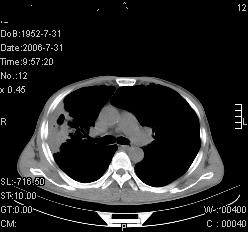

患者,男,54岁,咳嗦,咳痰20天。抗炎治疗2周。现esr76mm/h,目前患者症状明显好转,但发现两次ct片未见明显变化。两次分别做与7.25、7.31。第一次诊断右肺上叶炎症累计胸膜。大家看,从影像上内排除结核吗?

结核的可能性非常大,右上肺病变应该考虑干酪性肺炎。理由:

1.纵隔内多发淋巴结肿大。

2.esr76mm/h。

3.虽经抗炎治疗肺窗病灶有所吸收、减小,但纵隔窗病灶形态、密度、范围无明显变化。如果是单纯的大叶性肺炎,“抗炎治疗2周,目前患者症状明显好转”病灶应该基本消散了,至少也处于吸收消散期,密度变淡、范围变小。同时本病例所示其内的密度不均匀,见多发大小不一空洞样影也不符合大叶性肺炎吸收消散期表现。

病灶特点:片状 索条 结节混杂影,部分融合,密度不均,广泛累及相应胸膜.

临床治疗;二周未吸收.但症状好转.

多考虑:肺结核.